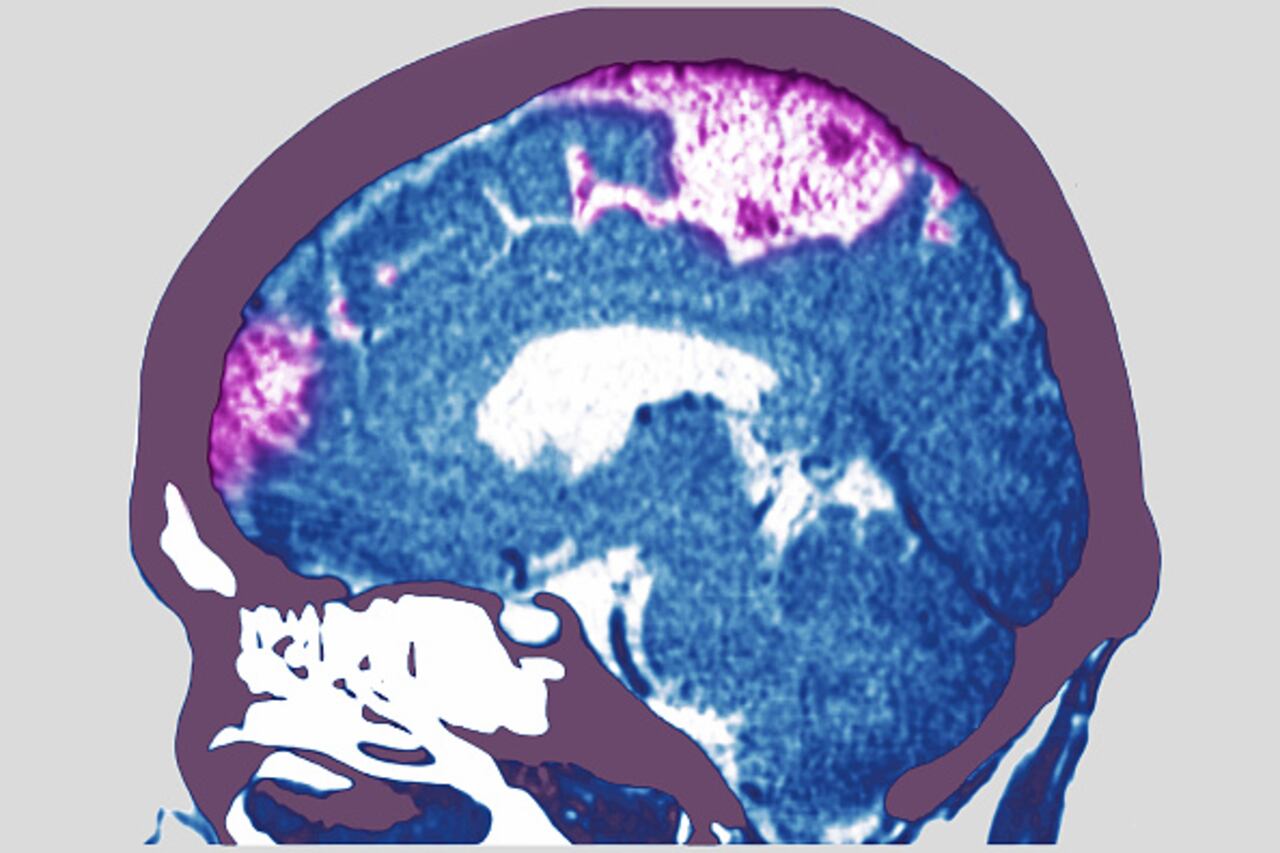

Un ataque cerebral, clínicamente llamado accidente cerebrovascular, ocurre cuando el flujo de sangre hacia el cerebro se ve alterado, lo que provoca que una región cerebral comience a morir al no recibir el oxígeno y nutrientes necesarios para su funcionamiento.

Los ataques cerebrales se dividen en dos categorías principales: los isquémicos, causados por la obstrucción de un vaso sanguíneo por un coágulo, y los hemorrágicos, provocados por la ruptura y sangrado de un vaso sanguíneo en el cerebro.